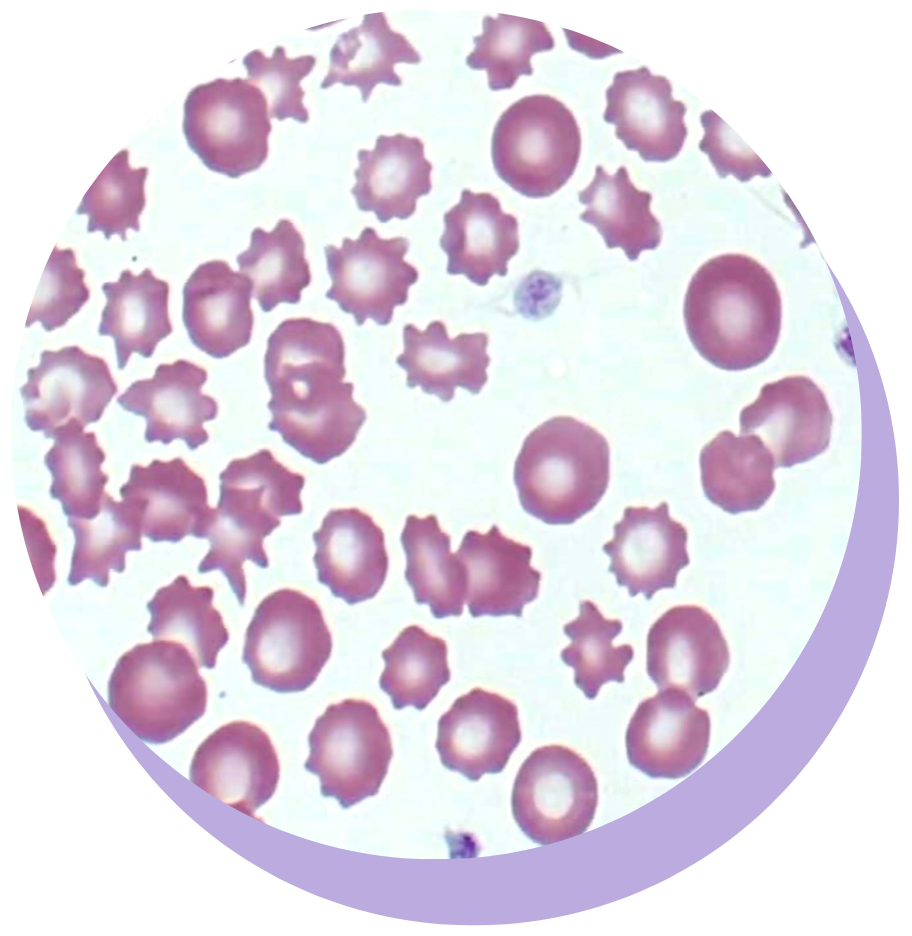

MASTERING HEMATOLOGY: PRACTICAL APPROACH TO CBC AND BLOOD SMEAR INTERPRETATION

Strengthen your identification skills and use that information in conjunction with the CBC to interpret what abnormalities mean for the patient.